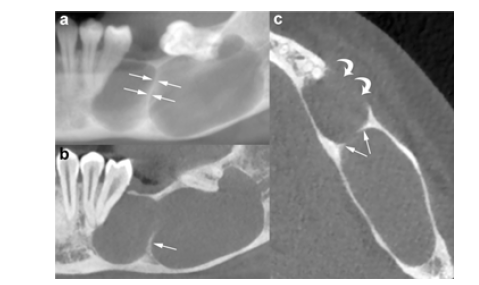

Panoramic radiography provides a two-dimensional depiction of the curved maxillary and mandibular dental arches and serves as a valuable initial tool for evaluating odontogenic lesions, including OKCs. It assists in assessing lesion location, size, morphology, margins and overall extent. However, its diagnostic capability is limited by inherent drawbacks such as magnification, geometric distortion and superimposition of anatomical structures. Consequently, three-dimensional imaging is often requiredparticularly for larger lesions-to obtain more accurate preoperative information. On panoramic images, OKCs typically present as welldefined unilocular or multilocular radiolucent lesions bordered by a corticated rim (Figure 1). The unilocular pattern is more frequently observed, whereas multilocular lesions occur in roughly 30% of cases and are more common in the mandible [9]. In mandibular unilocular OKCs, a few thin or incomplete internal septa may be visible, a feature more commonly associated with larger lesions.

Figure 1:

Mandibular odontogenic kerato-cysts (Okc’s)

a. Cropped panoramic radiograph illustrating a unilocular

lesion in the posterior mandible and ramus, causing mesial

displacement of the impacted third molar (curved arrow).

b. Cropped panoramic radiograph showing a multilocular

lesion involving the posterior mandible and ramus, exhibiting

a characteristic soap-bubble appearance.

A cropped panoramic radiograph reveals a large OKC with well-defined, lobulated borders (arrowheads) occupying the mandibular body. An incomplete internal septum is also visible within the lesion (opposing arrows). Approximately 30% of OKCs are associated with at least one unerupted tooth-most commonly the third molars [9]. This association is observed more frequently in younger patients [15]. The radiographic characteristics of OKCs are not pathognomonic, especially in small unilocular lesions [15]. When a small unilocular OKC appears in the anterior maxillary sextant, it may mimic other odontogenic or non-odontogenic cysts, such as radicular cysts (Figure 1), lateral periodontal cysts or nasopalatine duct cysts [17]. Histologically confirmed OKCs. Cropped panoramic radiographs (a and b) demonstrate two unilocular radiolucent lesions (asterisks) with well-defined, corticated borders (arrowheads) located in the anterior maxilla between the roots of adjacent teeth. The radiographic appearance of these radiolucencies may mimic a radicular cyst. Large mandibular OKCs characteristically grow along the length of the mandible, showing minimal Bucco-lingual expansion, particularly within the mandibular body [15]. On panoramic radiography, this growth pattern typically presents as an extensive radiolucent lesion with significant mesiodistal extension and little or no cortical expansion (Figure 1 & 2). In contrast, large maxillary OKCs often produce marked expansion of the alveolar bone and may involve adjacent anatomical structures. Notably, when a maxillary OKC originates in the molar region, extension into the maxillary sinus is commonly observed (Figure 2) [22].